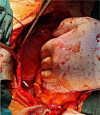

Accidental detachment of mechanical valve leaflet during implantation is a rare and potentially serious complication. When the lost leaflet cannot be found by direct visualisation, additional diagnostic procedures are necessary to detect it. Computer tomography is the best detection method, but the patient needs reoperation. We presented a patient in whom the detached leaflet migrated and became trapped into the left inferior pulmonary vein. The computed tomography (CT) scan was used to reveal leaflets, and successful extirpation was performed in the second operation.